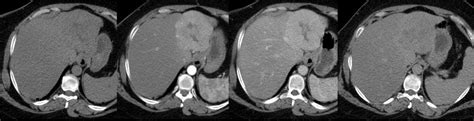

La diagnosi del danno cerebrale da radiazioni rappresenta una delle sfide più complesse per i neuroradiologi. Le lesioni indotte dalle radiazioni, in particolare la radionecrosi, appaiono spesso quasi identiche alla recidiva del tumore originale nelle immagini diagnostiche standard, rendendo difficile la differenziazione. Per affrontare questa sfida diagnostica, vengono impiegate diverse tecniche avanzate di imaging:

- Risonanza Magnetica (RM) con Contrasto: Questo esame costituisce la base per la valutazione del tessuto cerebrale. La somministrazione di un mezzo di contrasto può evidenziare aree di alterazione vascolare o infiammatoria, ma anche la recidiva tumorale.

- RM a Perfusione: Questa tecnica avanzata permette di misurare il flusso sanguigno cerebrale. Differenze nei pattern di perfusione tra lesioni da radiazioni e recidive tumorali possono aiutare nella diagnosi differenziale.

- Spettroscopia RM (MRS): La spettroscopia RM analizza la composizione chimica del tessuto cerebrale, fornendo informazioni su specifici metaboliti che possono variare tra le diverse patologie. Ad esempio, la presenza di N-acetilaspartato (NAA) ridotto e lattato aumentato può suggerire necrosi, mentre pattern differenti possono essere osservati in caso di recidiva tumorale.

La combinazione di queste tecniche di imaging, insieme a una scrupolosa valutazione clinica e anamnestica del paziente, è fondamentale per una diagnosi accurata.